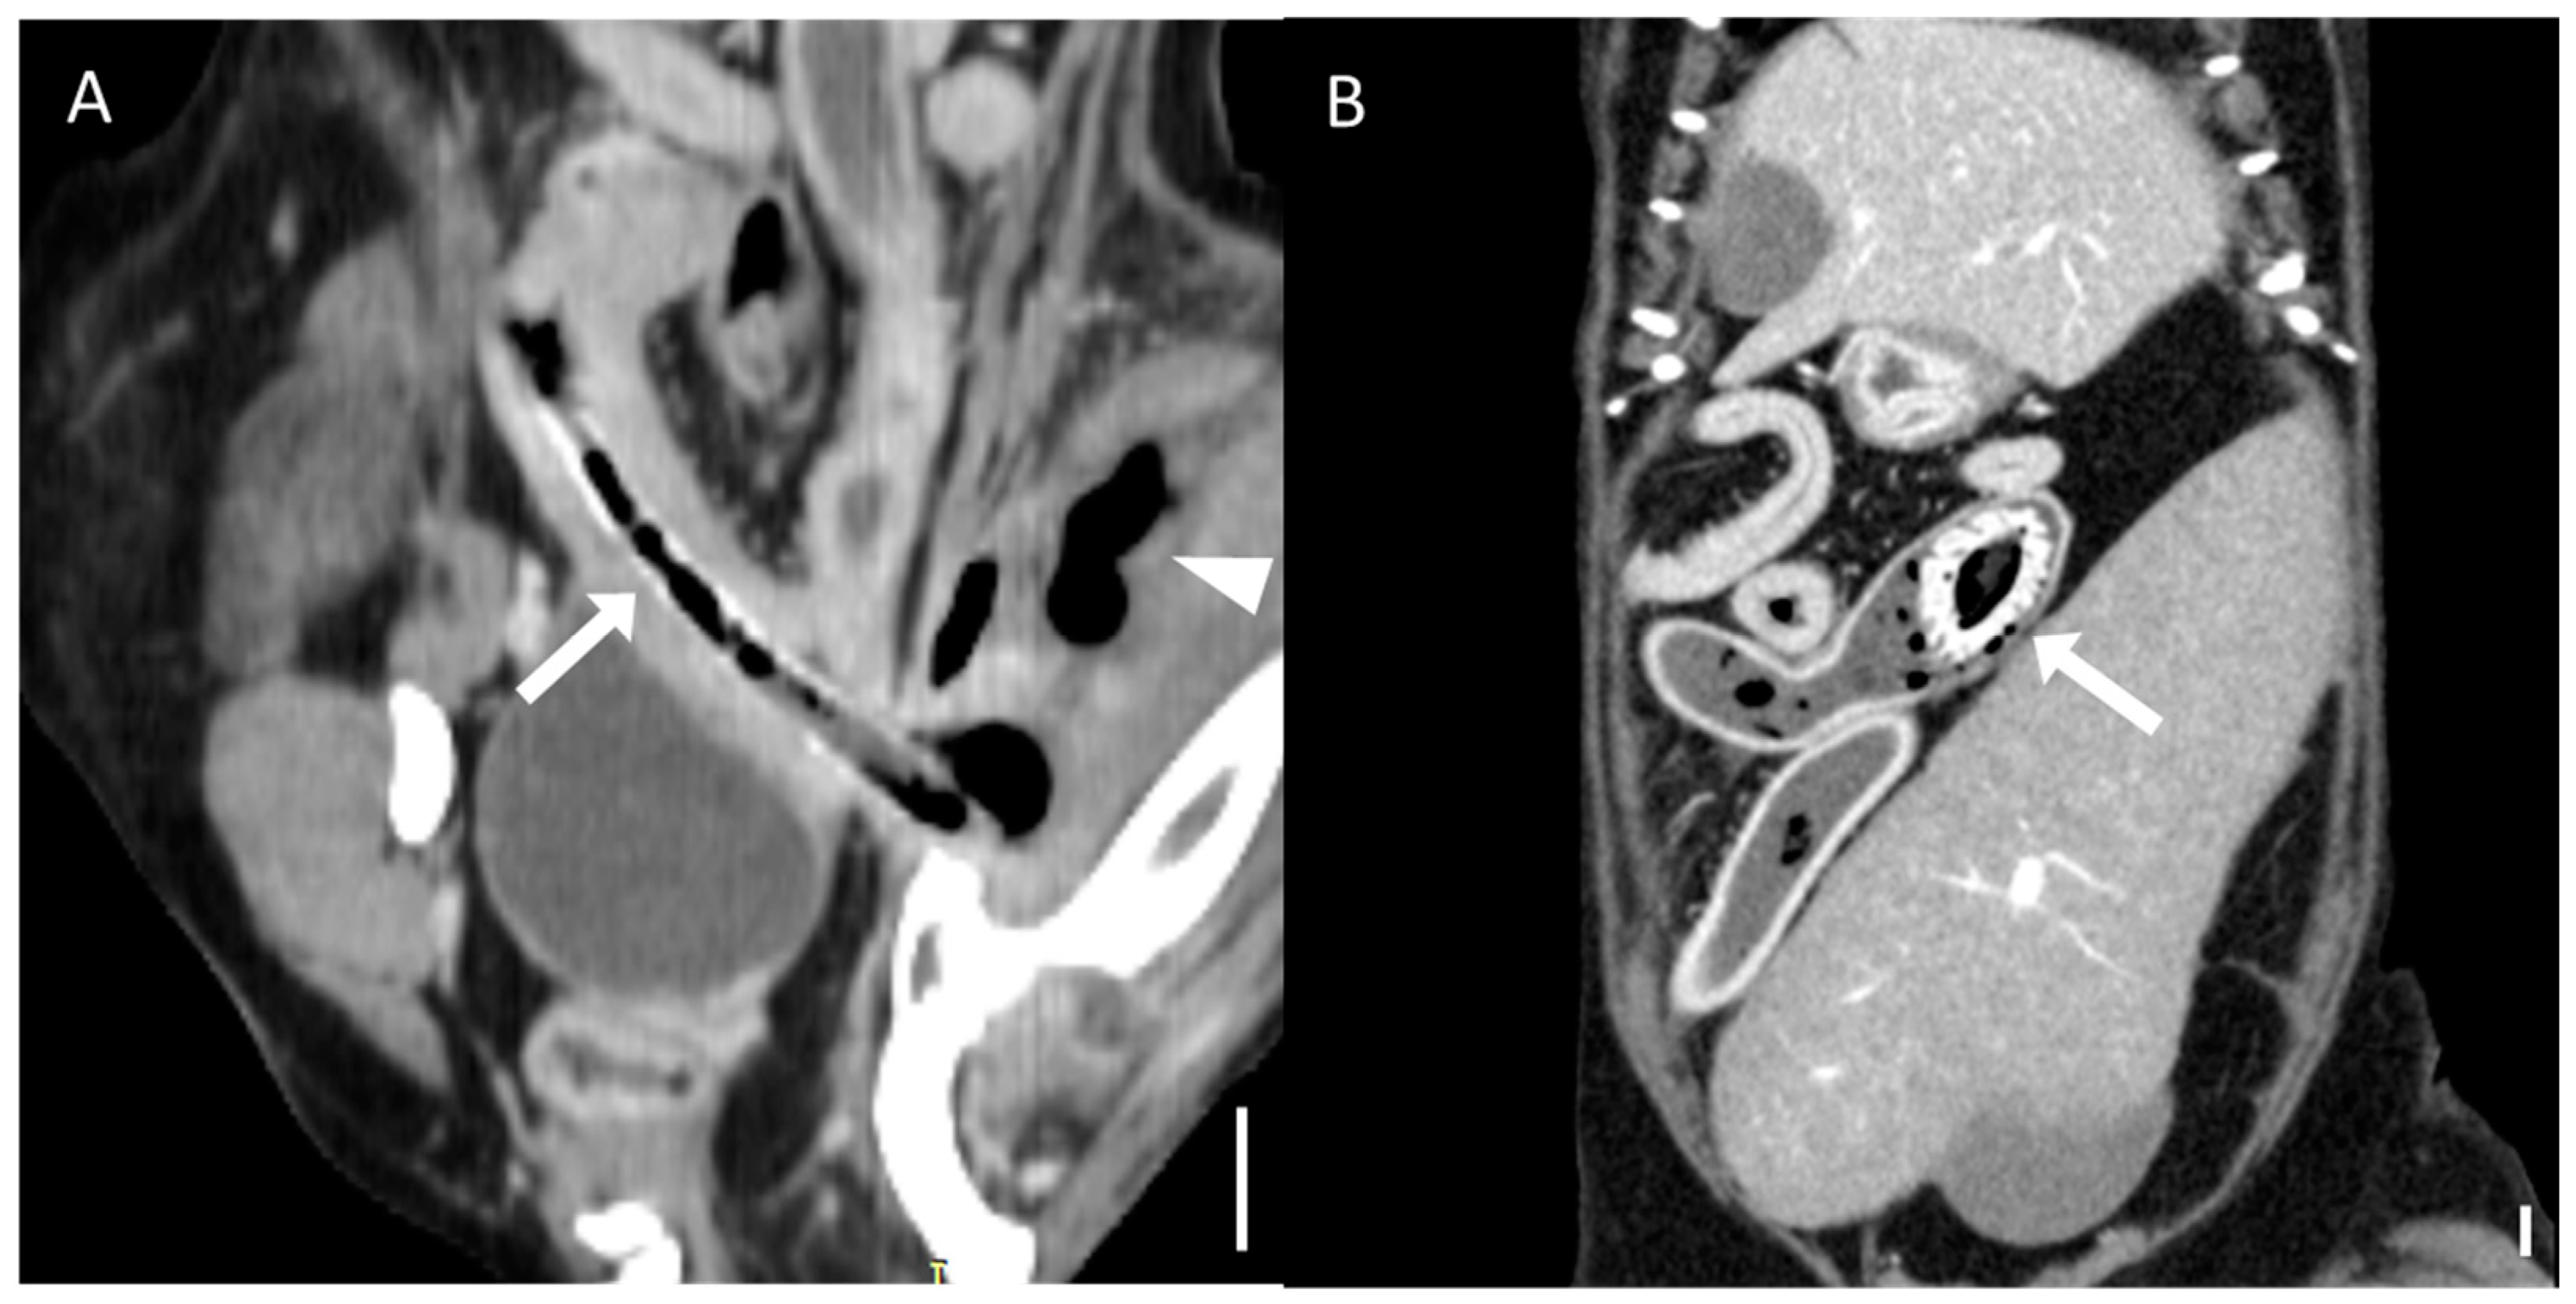

Figure 3. Representative CT images of foreign bodies affecting organs beyond the gastrointestinal tract (scale bar equals 1 cm) (A) Transverse CT image showing a dilated (8.6 mm) common bile duct (arrow) due to obstruction of the major duodenal papilla caused by a foreign body. The patient has duodenal obstruction resulting from a trichobezoar (arrowhead). (B) Sagittal CT image demonstrating a foreign body (arrow) penetrating the stomach wall and extending into the spleen (arrowhead). The patient underwent gastrotomy and splenectomy, and the foreign body was identified as a toothpick. CT, computed tomography.

Foreign bodies located in the duodenum were associated with a higher incidence of complications in this study, and bowel wall rupture was significantly linked to fatal outcomes. This can be explained by the complex anatomy of the duodenal region, which is closely related to the pancreas and bile ducts [28,29]. Duodenal obstruction may lead to severe secondary conditions, such as extrahepatic biliary obstruction and pancreatitis. Surgical management of duodenal lesions is also more complex and may require procedures such as cholecystoenterostomy, gastrojejunostomy, or pylorectomy in cases of extensive damage, often resulting in a poor prognosis [30]. Furthermore, bowel wall rupture, a complication significantly associated with adverse outcomes in this study, can lead to peritonitis, systemic inflammation, and septic shock [21,31,32].